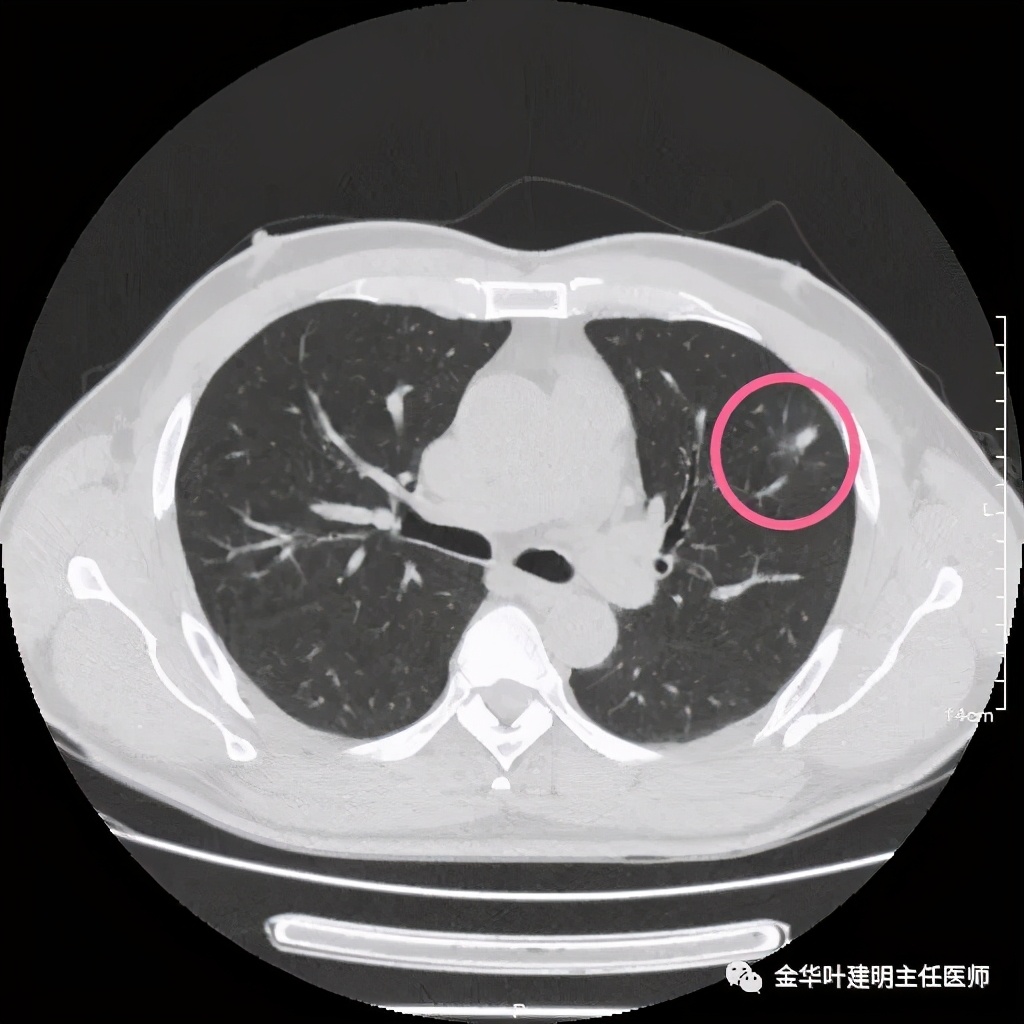

我们见左上实性病灶,主病灶旁有卫星灶,有血管进入,但也有贴边走行,边缘略显模糊,膨胀感与细毛刺不明显,收缩力也不明显。下面是其靶扫描的片子:

病灶实性,但收缩力弱,绿色箭头示病灶边缘有一圈晕征(模糊且均匀)

病灶实性,但收缩力弱,没有细毛刺征,实性部分比较圆润,绿色箭头示病灶边缘有一圈晕征(模糊且均匀)

此层面红色箭头示有卫星灶,粉色箭头示主病灶

红色示卫星灶,粉色示病灶,绿色示边缘晕征

此层面相对最不舒服,病灶表面不平整。桔色箭头示血管进入病灶,但仍有绿色箭头示病灶有晕征(边缘是模糊的,不似肿瘤那种细毛刺且相对清楚轮廓)

紫色箭头示病灶的边缘向内凹陷,说明无膨胀性,绿色示晕征,粉色箭头指向病灶

此层面示病灶呈三角形,缺乏膨胀性,边缘较直,没有毛刺征,实性部分没有收缩纠集感,绿色箭头示晕征